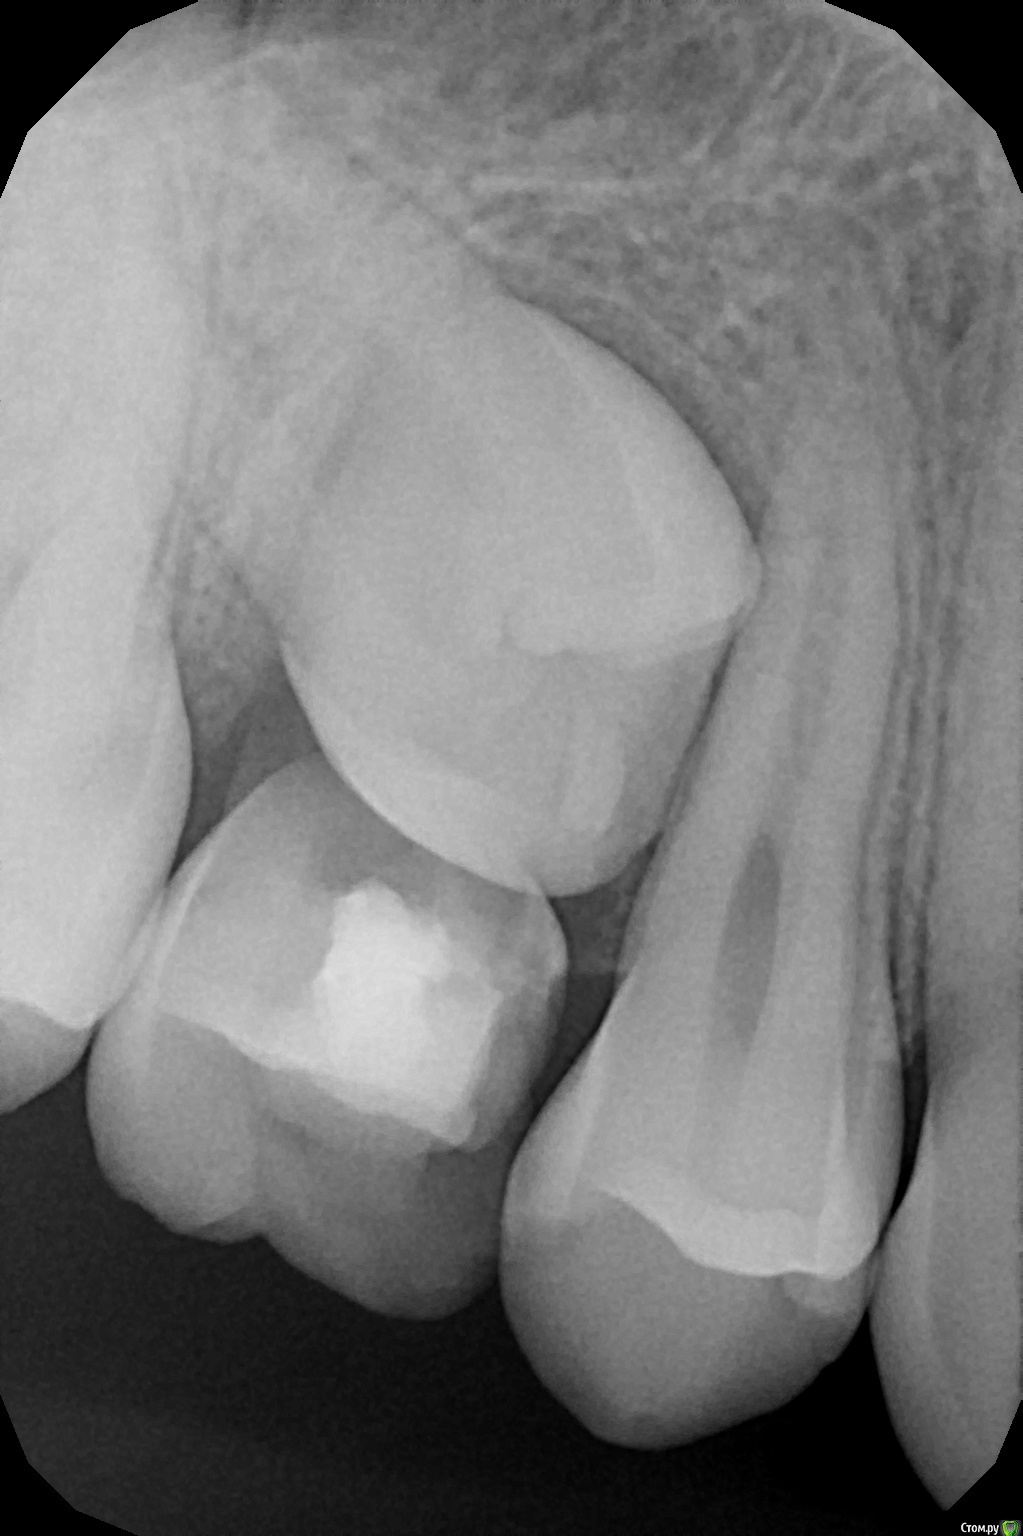

crown Опубликовано 14 марта, 2017 Поделиться Опубликовано 14 марта, 2017 12 лет, 55 "резорциненный", сегодня удалил, что делать с зачатком? Встанет ли он на место? Ссылка на комментарий

Opdihatop Опубликовано 14 марта, 2017 Поделиться Опубликовано 14 марта, 2017 Возможно... Пол-года подождите, а затем повторный снимок и контроль. Ссылка на комментарий

azerty Опубликовано 16 марта, 2017 Поделиться Опубликовано 16 марта, 2017 Тоже подождал бы полгода, а дальше скорей всего брекеты или другие методики, думаю сам не выйдет. Ссылка на комментарий